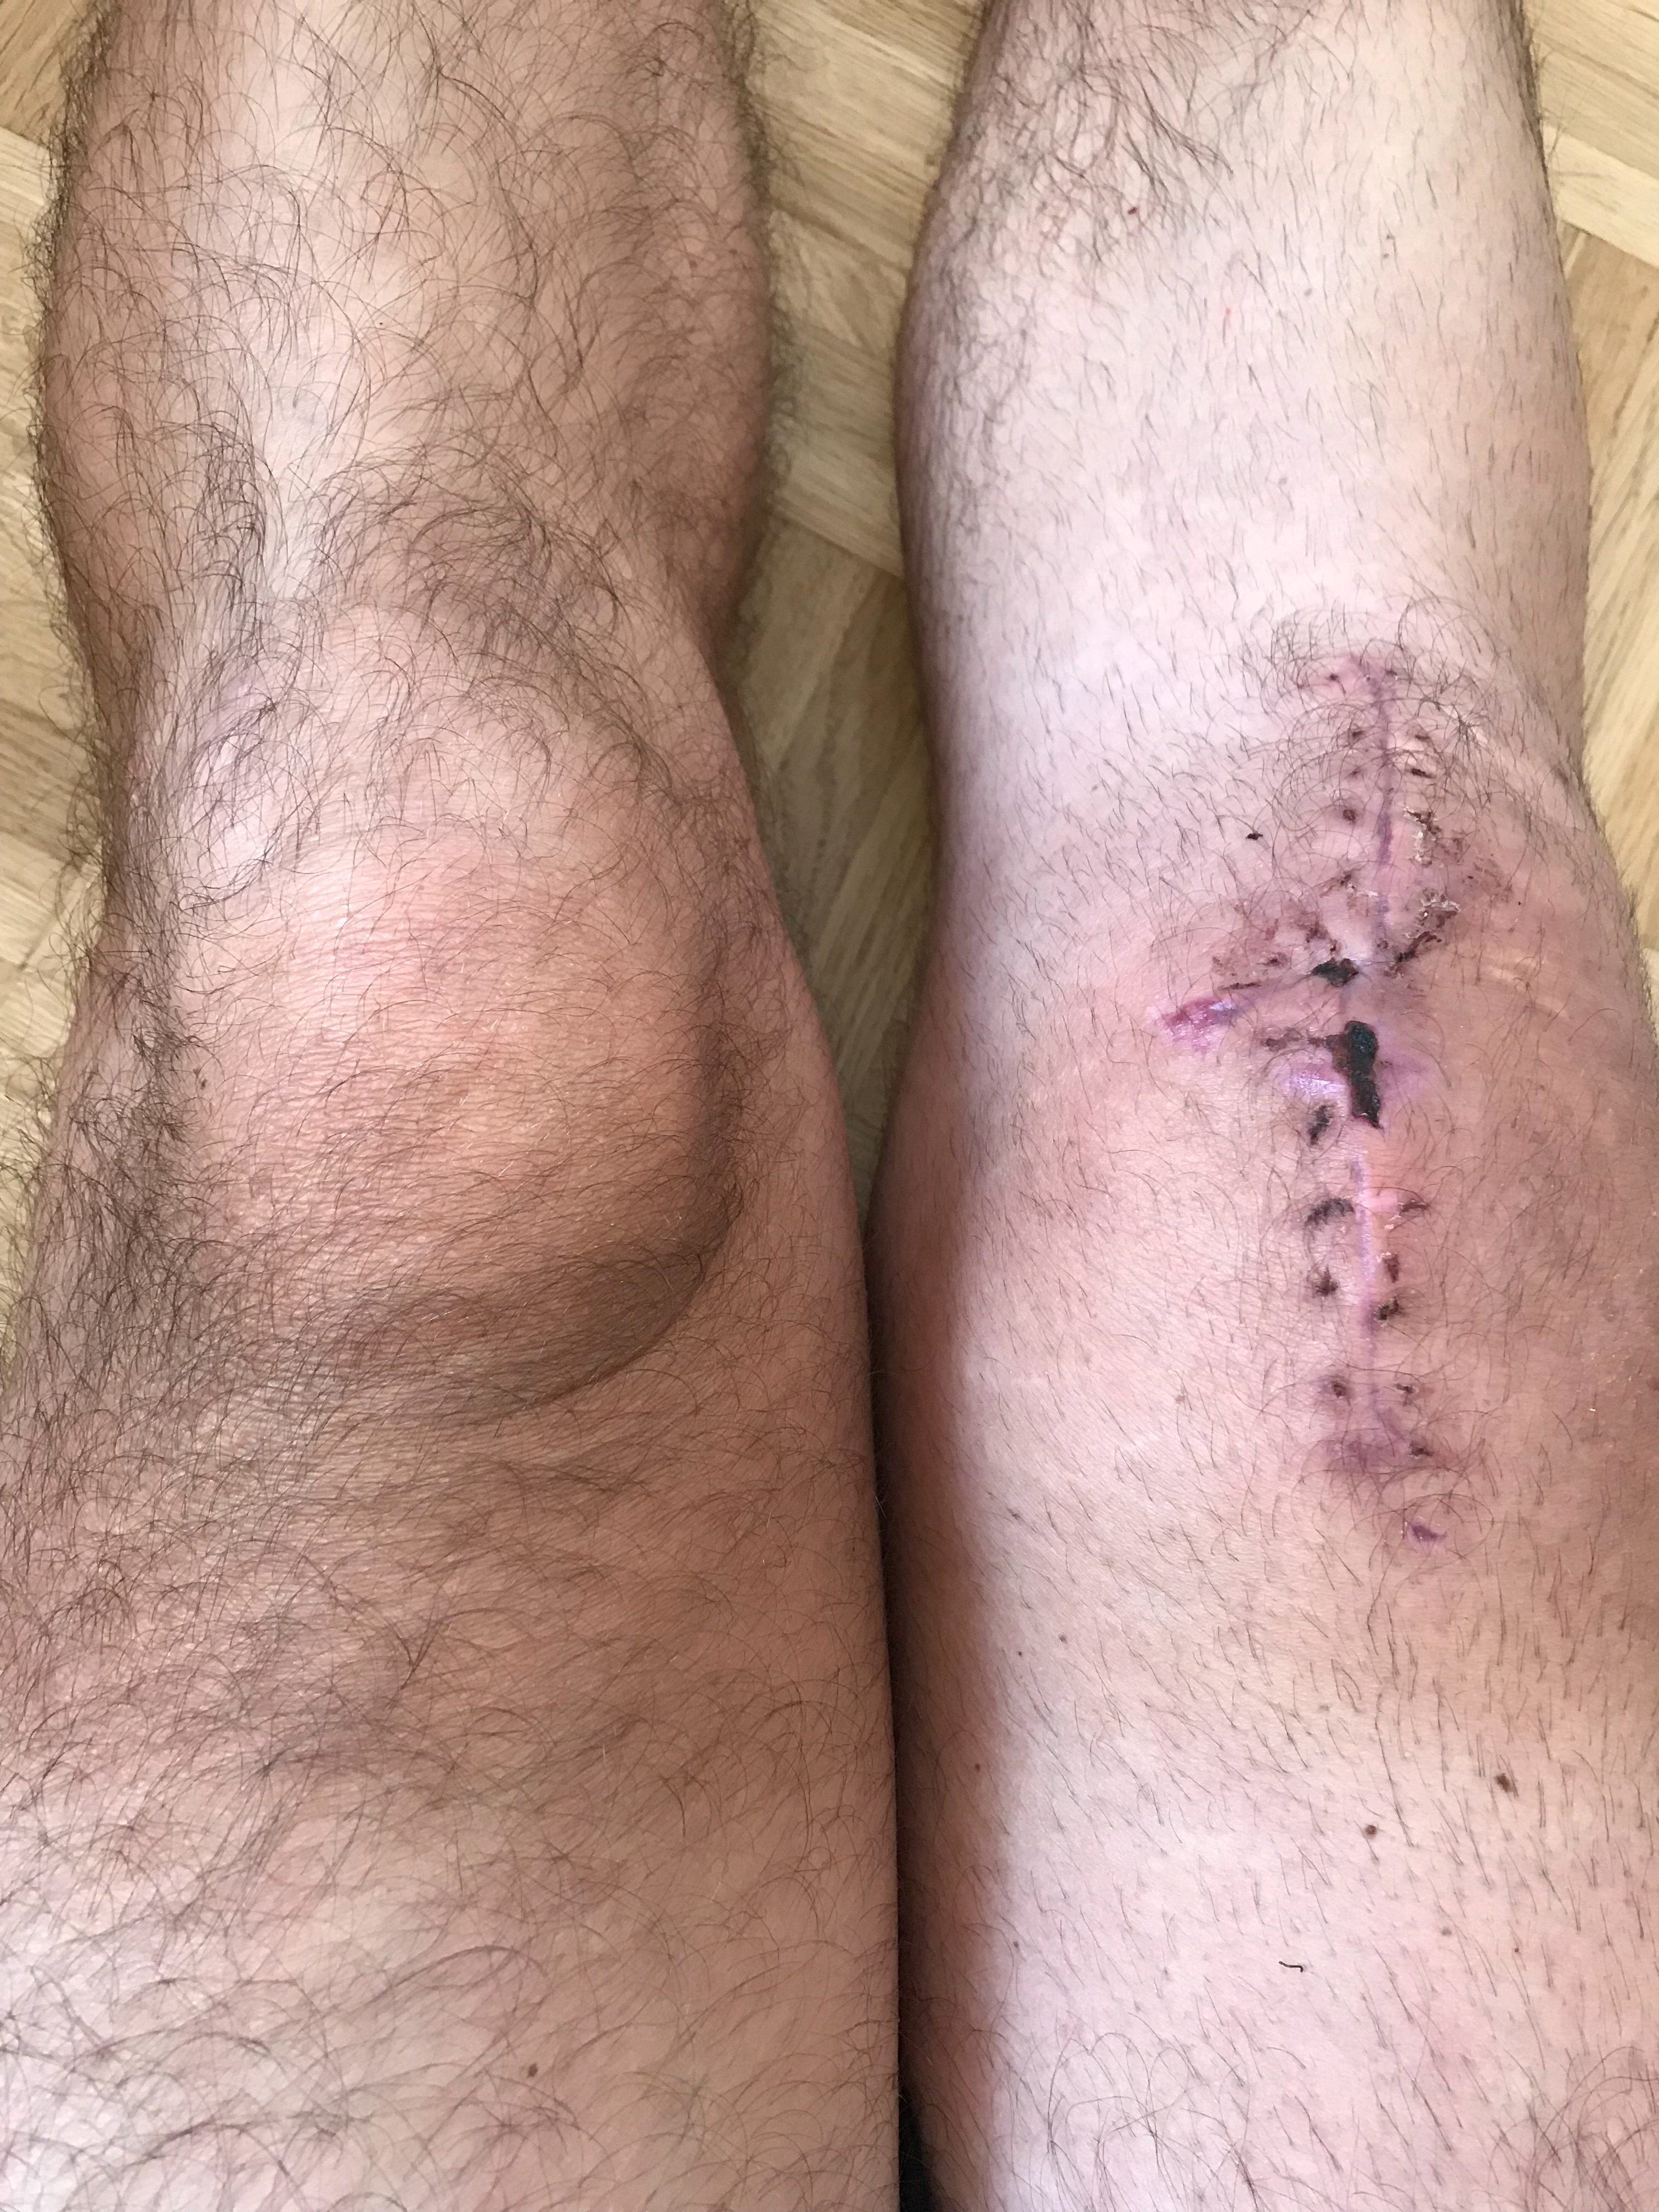

Within three hours, I found myself in the operating theatre, with Professor Doktor Doktor Reinhard Hoffmann – the medical director of BGU – leading the surgery.

Right after waking up from surgery, somebody told me the surgery had gone really well. On the next day, Herr Professor Doktor Doktor on the ward round told me so himself.

After surgery, my leg was totally immobilised for one week. Over the first couple of days, there was a tube sticking in the knee. With regard to pain, these days were by far the worst. I could barely sleep.